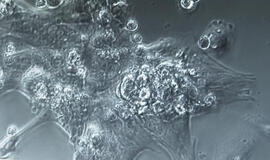

Laboratorijoje išaugintos širdys, pagamintos iš žmogaus kamieninių ląstelių, yra naudojamos mokyti dirbtinį intelektą aptikti širdies ligas